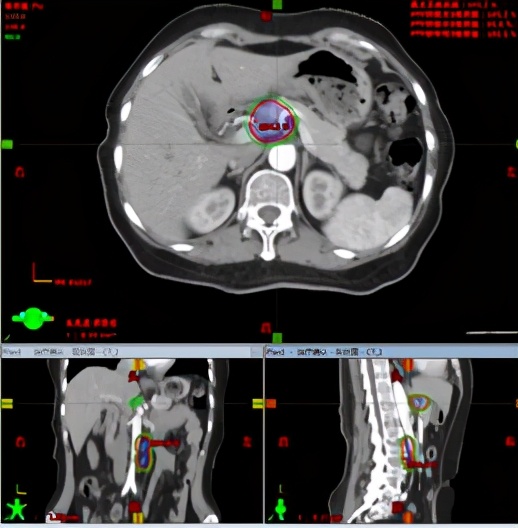

SBRT:胰体部病灶+腹膜后淋巴结病灶,剂量24GY/3F。

放疗计划